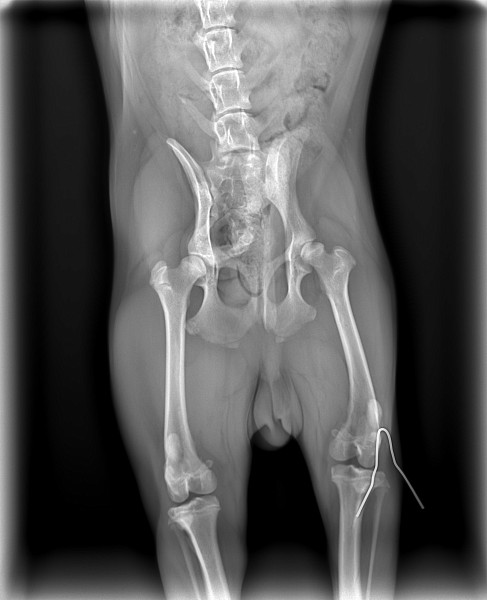

Дисплазии задних лапах